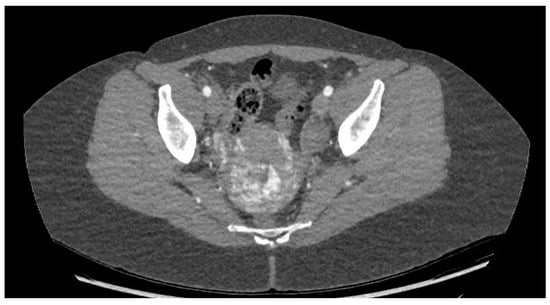

Ultrasonography showed an endometrial cavity occupied by a protruding formation in the uterine cavity measuring 38 × 15 mm, compatible with a uterine AVM (Figure 1). The presence of vascularisation of the right lateral uterine wall was noted, and pulsed Doppler showed a peak systolic velocity > 100 cm/s (Figure 2).

Figure 2. Colour and pulsed Doppler studies of the uterine arteriovenous malformation.